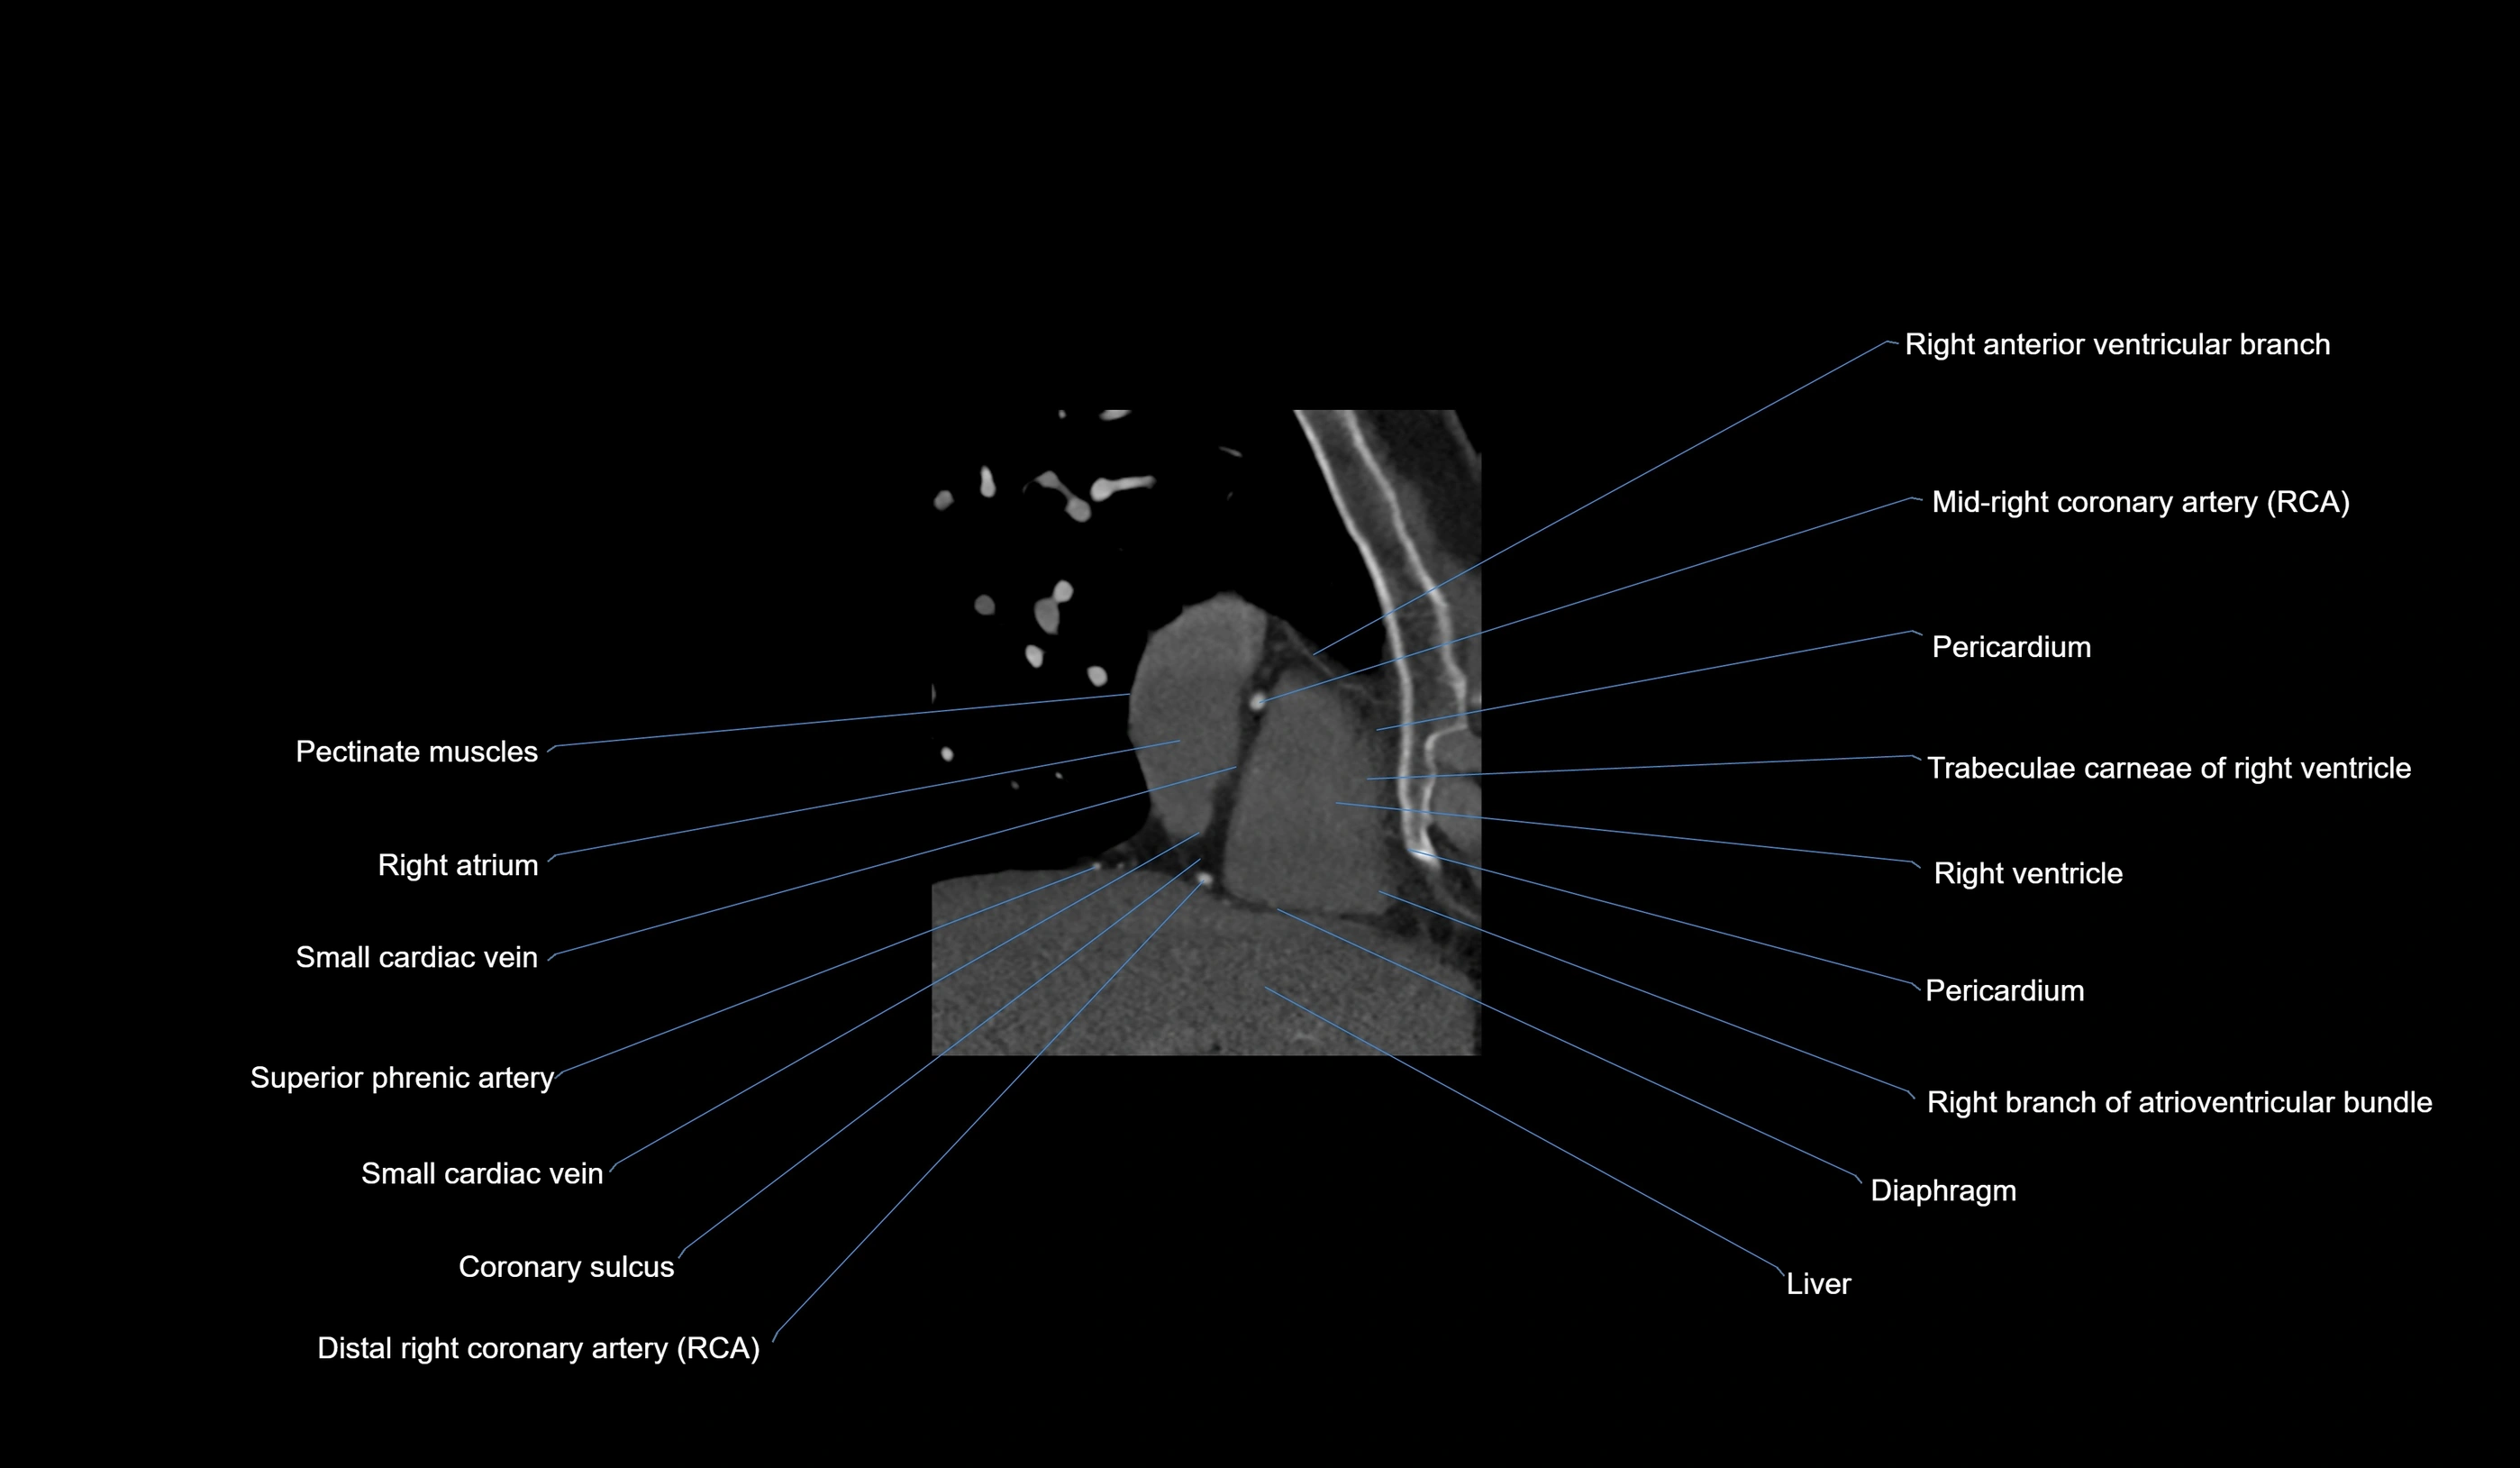

CT images